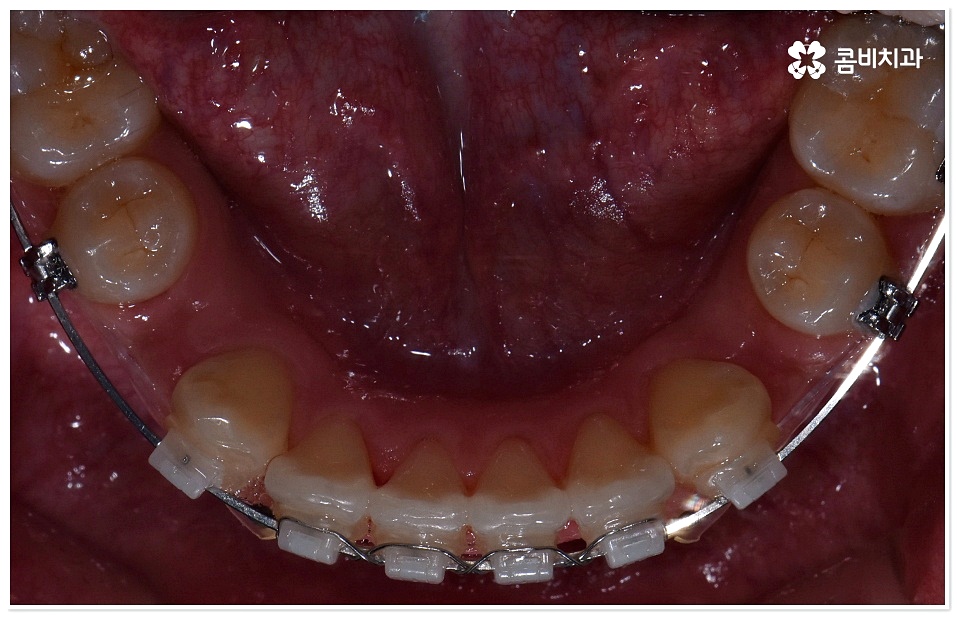

하지만 막상 덧니치아교정 을 받고 싶어도 실제로 시작하기까지 여러 가지 망설여지는 포인트가 있으실 거예요. 그 중에서도 겉으로 드러나는 장치 때문에 부담을 느끼시는 분들이 있을 수 있는데 최근에는 관련 의료 기술이 발전하면서 교정 장치가 눈에 덜 띄도록 하는 방법과 장치들이 나와 환자분들이 느끼시는 심미적인 부담을 줄여주고 있으니 먼저 검진 및 상담부터 받아보시길 권유드리고 있어요. 특히 교정치료 기간 동안 스스로 탈착이 가능한 투명교정 등 환자의 상태에 맞춘 다양한 방법을 알아볼 수 있으니 숙련된 의사선생님과 충분히 상담한 후 자신에게 적합한 계획을 세우실 필요가 있어요.

교정은 또한 전체 과정 못지 않게 사후 관리가 중요한 치료라고 할 수 있어요. 교정 과정이 모두 끝난 다음 사후 유지 장치 착용을 소홀히 하면 원래 상태로 되돌아 가려고 하는 치주인대의 특성 때문에 치열이 다시 무너질 수 있으므로 보다 안정적인 덧니치아교정 치료 결과를 위해 사후 관리 역시 신경써서 해 주셔야 하는데 이 과정에서 처음부터 끝까지 책임있게 진료에 임하는 체계적인 케어 시스템을 갖춘 치과의 도움을 받으면 좋을 거예요.